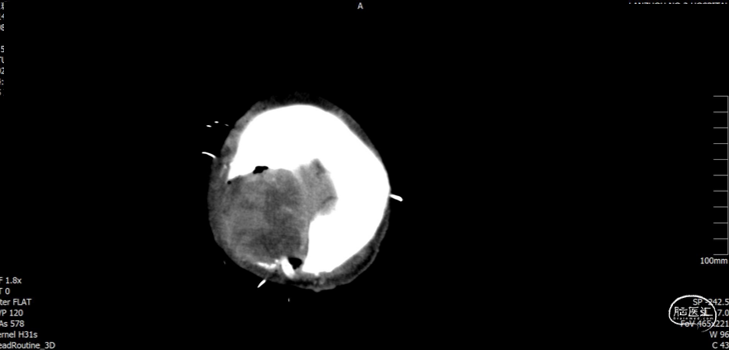

现病史:患者于入院前2小时在工地干活时被高空坠物砸伤头部(具体过程不详),伤后出现左侧肢体活动失灵,被同事送往我院急诊科就诊,入急诊时神志清醒,GCS15分,行颅脑CT提示:1. 右侧颞顶骨骨折,顶骨多发骨折并部分嵌插脑内;2. 右侧顶叶脑挫伤;3. 右侧额颞顶部硬膜下血肿;4. 蛛网膜下腔出血。急诊予以清创、止血及对症治疗。期间患者意识障碍加重呈嗜睡,GCS14分,我科急会诊后以“1. 开放性颅脑损伤特重型 1.1开放性颅内异物1.2脑挫裂伤1.3蛛网膜下腔出血1.4颞顶骨骨折(右);2. 偏瘫(左)”收住入院。自发病来,患者暂无抽搐、晕厥等症状,小便失禁。

入院查体:右顶部头皮见长约2.0cm开放性伤口,出血并脑脊液漏出,颅骨嵌入。神志嗜睡,GCS评分:E3+V5+M6=14分。双侧瞳孔等大正圆,直径均约3.0mm,直、间接对光反射灵敏。左侧上下肢肌力约I/0级,右侧上下肢肌力约IV/IV级。

入院检查